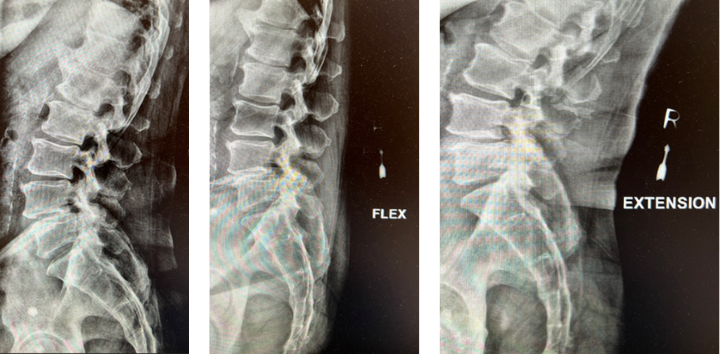

This is a 42-year-old otherwise healthy male who presented electively with progressively worsening neck pain radiating down the left arm, with paresthesia first three digits. He […]